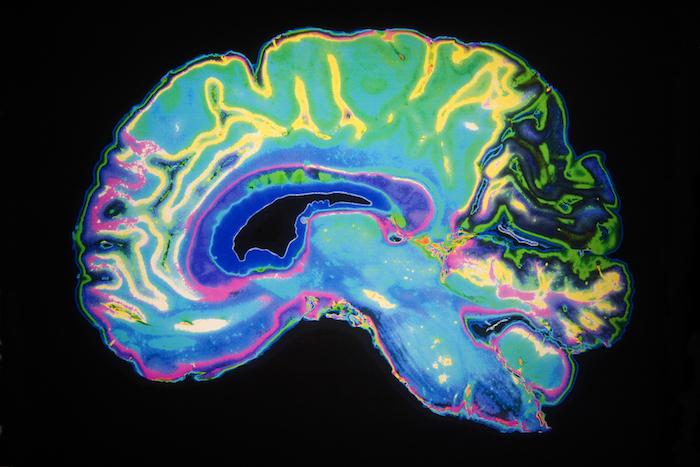

Fréquemment rencontrée chez les personnes âgées, la maladie d'Alzheimer est considérée comme une maladie neurodégénérative. Cela qui signifie qu'elle s'accompagne d'une perte significative et progressive des neurones et de leurs terminaisons nerveuses. Une étude franco-canadienne publiée dans Scientific Reports conteste maintenant ce point de vue.